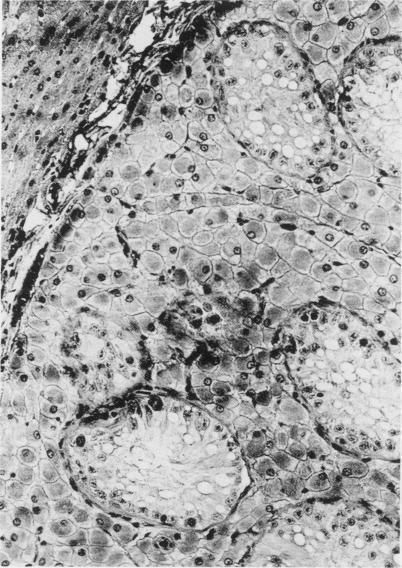

Some heterotopic tissue remnants in domestic animals.

Bundza A, Dukes T W

Can Vet J. 1978 Nov;19(11):322-4.